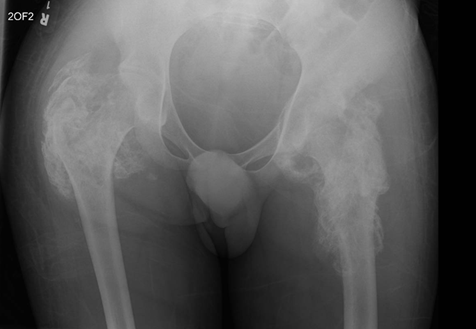

Figure 1.

Pelvic X-ray. Evidence of soft tissue calcification/ossification around

bilateral hip joints, indicating severe heterotopic ossification (HO).

(ROM). A pelvic X-ray and pelvic CT were therefore performed (Figure 1 and Figure 2). The pelvic

X-ray (Figure1) showed evidence of

soft tissue calcification/ossification around bilateral hip joints, indicating

severe heterotopic ossification (HO). The pelvic CT (Figure 2) in coronal view similarly depicted heterotopic

ossification involving bilateral hip joints.